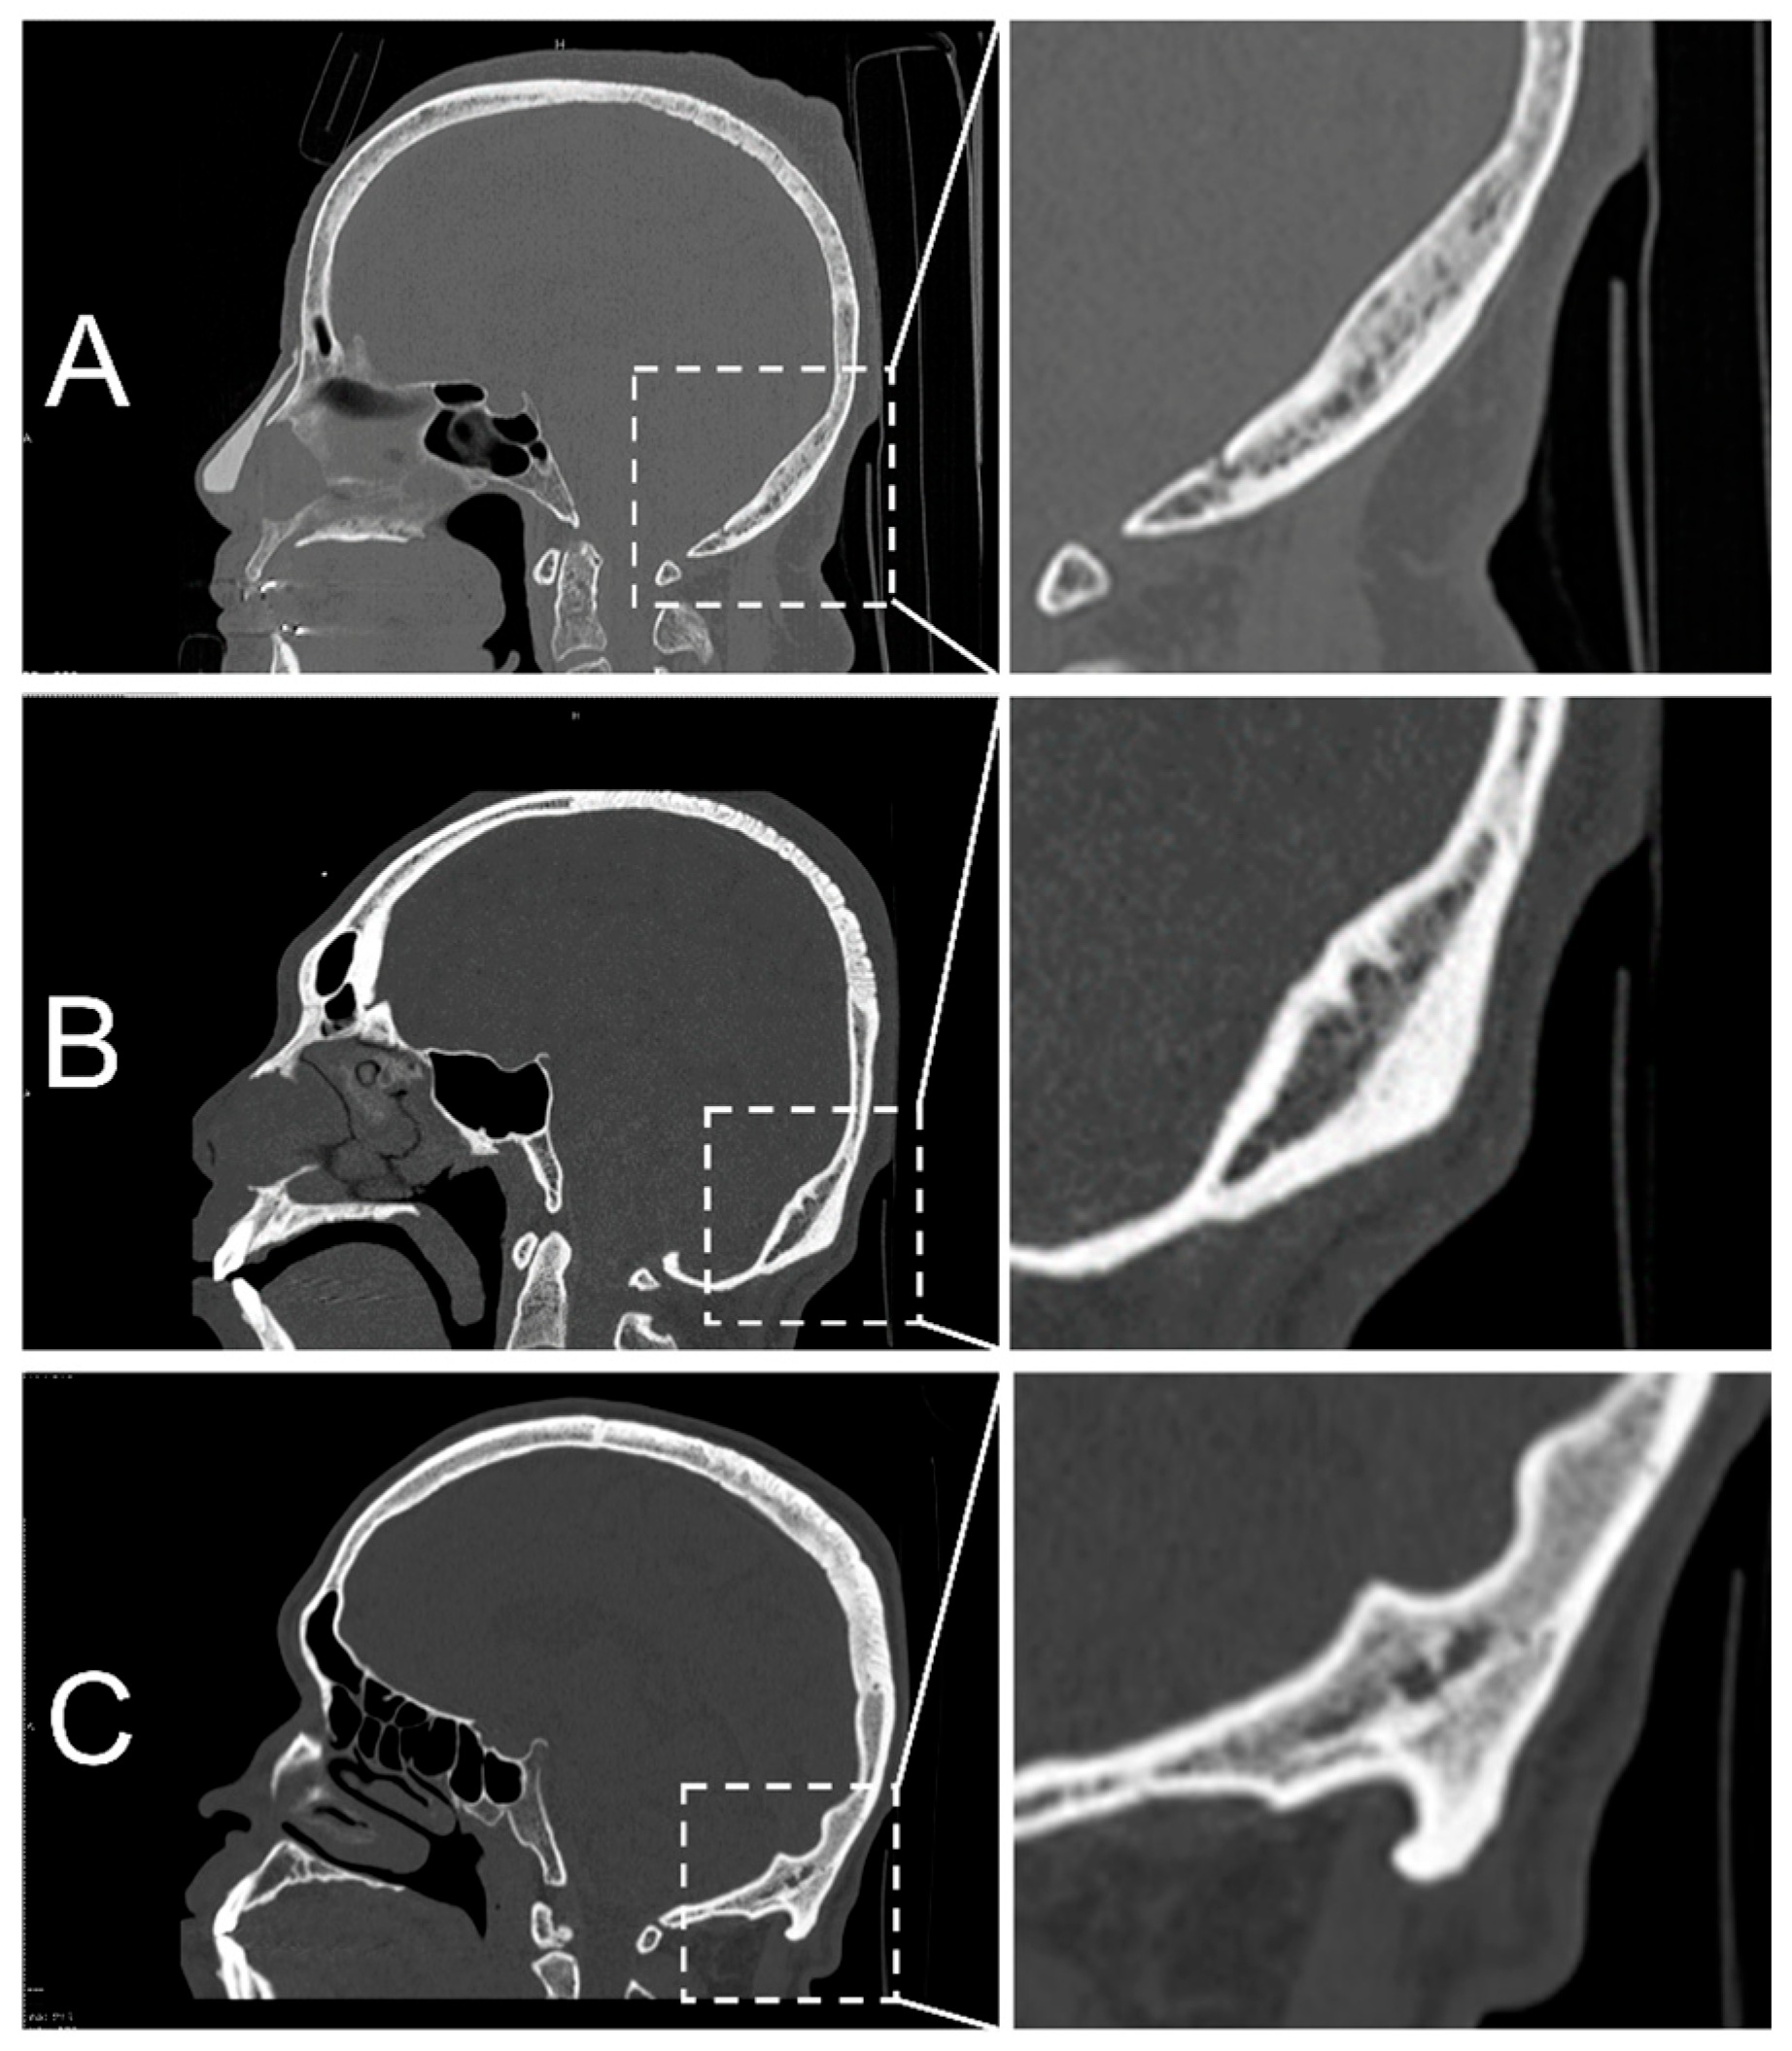

2.4. Classification of EOP Types

2.5. Morphometric Measurements

3.2. Types and Prevalence of EOP Observed in CT Scans and Dry Skulls

| Types of EOP | Prevalence of EOPs Investigated in the Northeastern Thai Population | |||||||

|---|---|---|---|---|---|---|---|---|

| CT Scans (n, 750) | Dry Skulls (n, 1060) | |||||||

| Total (n, 750) | Female (n, 375) | Males (n, 375) | Total (n, 1060) | Unidentified Sex (n, 187) | Identified Sexes | |||

| Total (n, 873) | Female (n, 399) | Male (n, 474) | ||||||

| I (flat) | 185 (24.7%) | 139 (37%) | 46 (12.3%) | 226 (21.3%) | 41 (21.9%) | 185 (21.2%) | 131 (32.8%) | 54 (11.4%) |

| II (crest) | 421 (56.1%) | 199 (53%) | 222 (59.2%) | 685 (64.6%) | 124 (66.3%) | 561 (64.3%) | 228 (57.1%) | 333 (70.3%) |

| III (spine) | 144 (19.2%) | 37 (10%) | 107 (28.5%) | 149 (14.1%) | 22 (11.8%) | 127 (14.5%) | 40 (10%) | 87 (18.4%) |